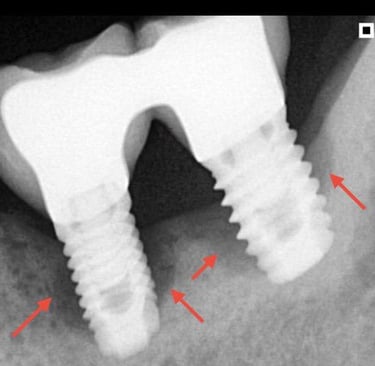

Aspecto Radiográfico Final com Implantes e Coroas

Implante com secreção, sangramento ou partes metálicas expostas?

Isso pode ser peri-implantite, uma inflamação que, quando não tratada a tempo, costuma levar à remoção do implante. A avaliação precoce é fundamental para escolher o melhor tratamento e preservar sua saúde bucal.

Implantes perdidos por peri implantite - Imagens originais — nenhuma contém retoques

Implante feito por outro profissional há cerca de 5 anos desenvolveu inflamação, saída de pus e gengiva inflamada, indicando peri-implantite, uma infecção que pode comprometer o implante se não tratada.